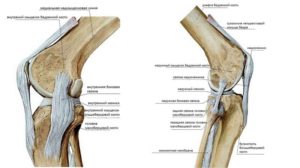

Анатомия

Коленный сустав состоит из бедренной, большеберцовой и надколенной кости. Внутри него расположены медиальные и латеральные хрящевые прослойки, выполняющие двигательную и стабилизирующую функции.

Так как на колено всегда приходится большая нагрузка, оно укреплено со всех сторон большим количеством связок. Связки надколенника очень прочные и способны выдерживать любую нагрузку.

Они подразделяются на два типа:

- Сухожилия, расположенные снаружи коленного сустава (малоберцовая и большеберцовая коллатеральные связки, косая связка, дугообразная и надколенная связка);

- Сухожилия, расположенные внутри сустава (задняя крестообразная связка, передняя крестообразная связка).

Наружные и внутренние сухожилия образуют поддерживающие связки надколенника. Кроме соединения костей, связочный аппарат вместе с сухожилиями выполняют функции стабилизации сустава.

Малоберцовая коллатеральная связка прикрепляется к головке малоберцовой кости и ведется от наружного надмыщелка бедренной кости.

Большеберцовая коллатеральная связка располагается от внутренней части надмыщелка до внутренней стороны большеберцовой кости и способствует удержанию голени от наружного отклонения.

Крестообразные сухожилия удерживают сустав от смещения вперед и назад.